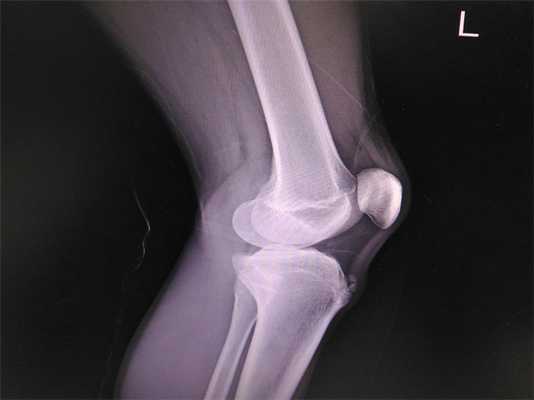

Для постановки окончательного диагноза рекомендовано рентгеновское исследование: выполняют снимок в прямой и боковой проекции.

Рентгенологические исследования суставов предназначены для поиска травм и других патологических изменений.

Решающим фактором в вынесении однозначного диагноза болезнь Осгуда-Шлаттера у детей и подростков была и остается рентгенография, которую с целью повышения информативности течения патологии лучше всего проводить в динамике. Для исключения прочих ортопедических заболеваний подобное обследование пораженного коленного сустава необходимо осуществлять в двух проекциях, а именно в боковой и прямой.

В начальной фазе развития заболевания на рентгенологических снимках отмечается уплощение бугристости большеберцовой кости в ее мягкой части и подъем нижнего края просветления, отвечающего расположенной в передней доле коленного сустава жировой ткани. Последнее несоответствие норме вызвано увеличением размера поднадколенниковой сумки, происходящее вследствие ее асептического воспаления. Какие-либо видимые изменения в самом ядре окостенения на этом этапе болезни Шляттера чаще всего отсутствуют.

Рентгенография коленного сустава при болезни Осгуда-Шлаттера

При прогрессировании патологии рентгенологическая картина меняется в худшую сторону. На снимках наблюдается сдвиг ядра окостенения на 2-5 мм вверх и вперед по отношению к стандартному расположению бугристости или его фрагментация. В некоторых случаях может отмечаться неровность естественных контуров и нечеткость структуры ядра окостенения, а также признаки постепенного рассасывания его частей, однако чаще всего происходит его срастание с основным телом кости с формированием костного конгломерата в форме шиповидного выступа. Такая характерная для болезни Шлаттера «шишка» на поздних этапах заболевания особенно хорошо видна на боковой рентгенограмме и явно прощупывается при пальпации в районе бугристости.